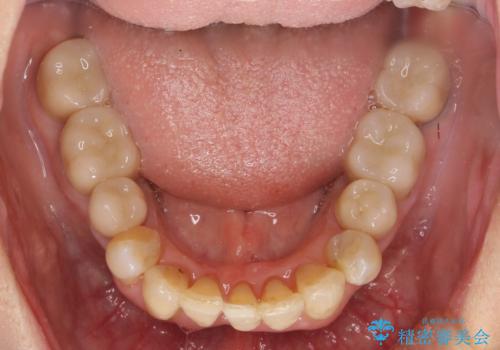

- 上顎前歯の黒ずみの改善、下顎前歯の十度なガタつき、矯正治療とセラミック治療を含む全体的な治療を希望され来院されました。

銀歯を高強度の仮歯に替えたのち、下顎前歯のみの部分矯正→全体的なマウスピース矯正治療(インビザライン)→最終的なセラミック治療と治療を進めます。

矯正治療と目立つ銀歯のやりかえを行ったことでかみあわせだけでなく、審美性・清掃性も改善し口腔内の環境を劇的に改善することができました。